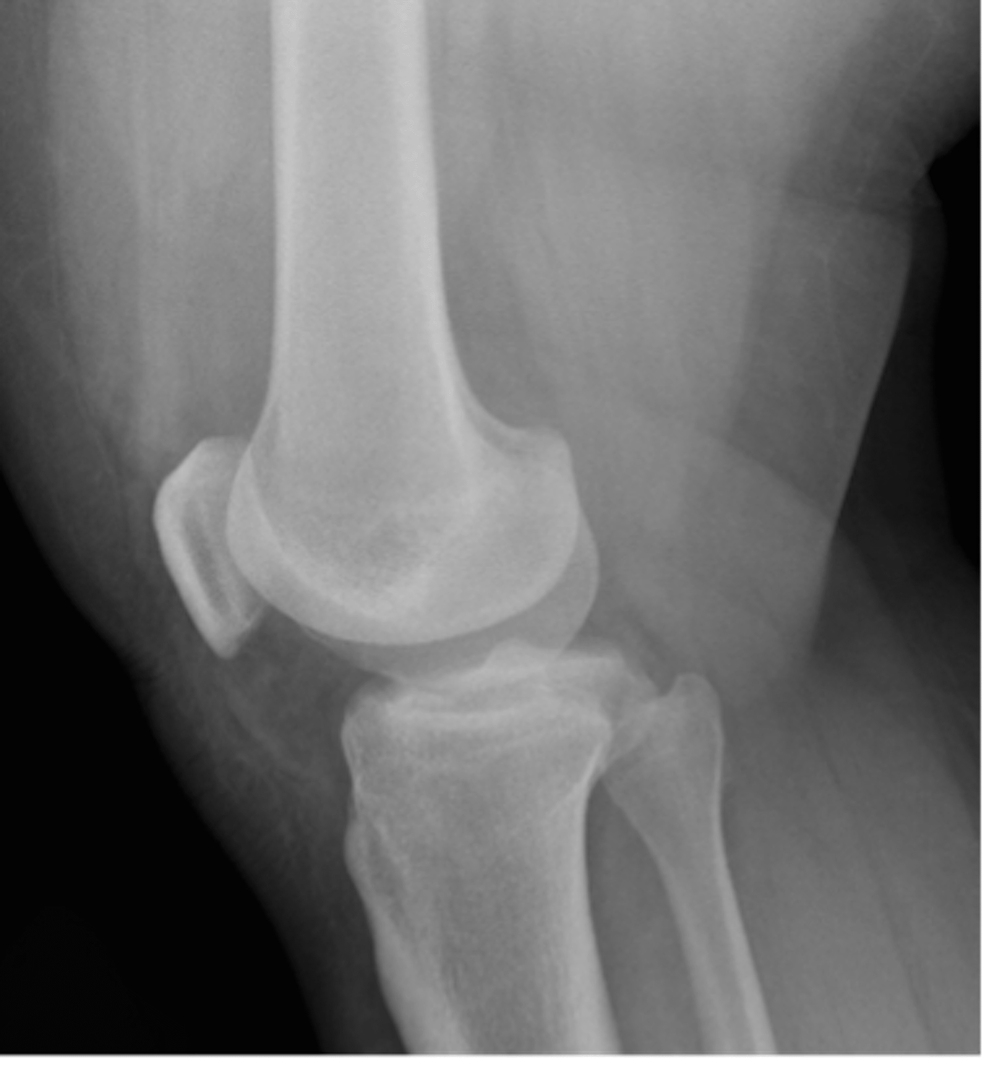

Figure 1 from Locking knee after intraarticular migration of broken Locked Knee Due To Patellar Infection (septic arthritis or osteomyelitis) redness,. Where a large torn section of cartilage gets wedged in the knee joint so it. Locked knee refers to an inability to either bend or straighten the knee. This article outlines two types and their associated symptoms and causes. Quadriceps or patellar tendon rupture is suspected. We also discuss the available treatments. A true. Locked Knee Due To Patellar.